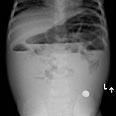

חיי פעוטה בת שנה ו-3 חודשים ניצלו בניתוח חירום: הפעוטה הובהלה למרכז הרפואי קפלן ביום חמישי האחרון, לאחר שהגיעה בשל בטן תפוחה משך מספר ימים, כאבי בטן, ירידה במשקל וחוסר תיאבון. בצילום שנעשה במחלקה נראה בבירור גוף זר כלשהו.

צילום הרנטגן. הסוללה נראיתה בבירור